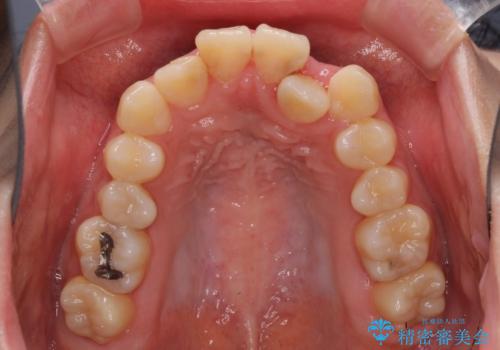

- 上下のデコボコと前歯のクロスバイトを改善したいとのことで来院された患者様です。

極力短期間で治療したいとのことで、ワイヤー装置による矯正治療を行うこととしました。